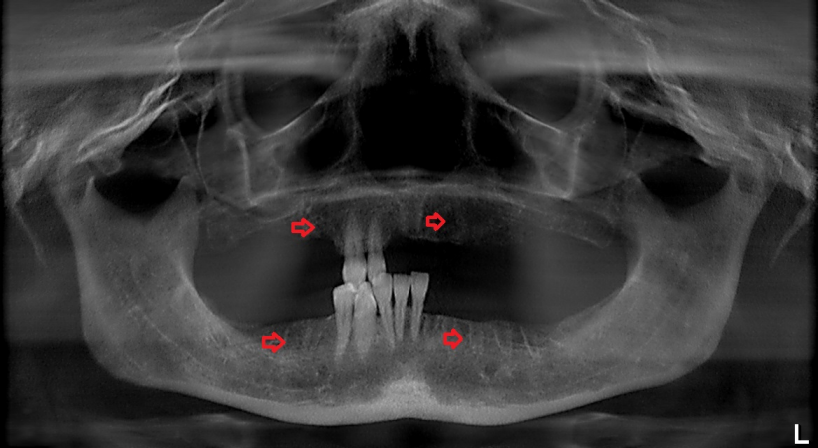

A panoramic radiograph obtained on the day of her visit on March 2017 revealed regions of osteosclerosis, subperiosteal bone deposition at the extraction sites, and persistent unremodeled bone in the alveolar sockets surrounded by periapical hypermineralized lines (Figure 2 [Fig. 2]). A generalized periodontitis combined with tooth loss and horizontal bone loss was also diagnosed radiologically. A digital volume tomography in sagittal view showed persistent bony trabecular architecture and absence of bony lysis – the classical radiologic signs of “persistent dry alveolar sockets” (Figure 3 [Fig. 3]).

Figure 2: Panoramic radiograph examination (performed in March 2017) revealed osteonecrosis, osteolysis, and subperiosteal bone deposition. Arrows show persistent unremodeled extraction sockets at surgical sites in the mandible and maxilla.